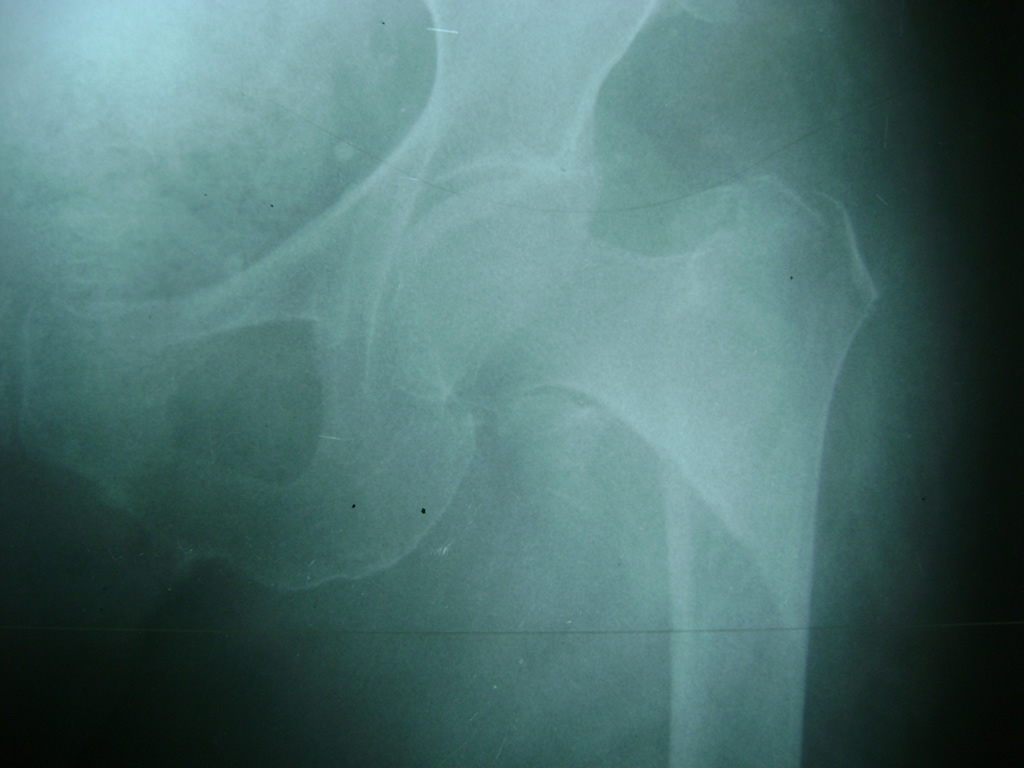

La cirugía de fractura de cadera se realiza para reparar una ruptura en la parte superior del hueso del muslo. Este hueso se denomina fémur.

Es parte de la articulación coxofemoral. Si una fractura de cadera no recibe tratamiento, es posible que deba permanecer en una silla o en la cama.

Esto puede llevar a otros problemas de salud potencialmente mortales, sobre todo si usted es una persona mayor.

A menudo se recomienda la cirugía para reparar la fractura debido a dichos riesgos.